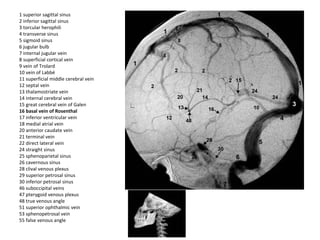

1 superior sagittal sinus

2 inferior sagittal sinus

3 torcular herophili

4 transverse sinus

5 sigmoid sinus

6 jugular bulb

7 internal jugular vein

8 superficial cortical vein

9 vein of Trolard

10 vein of Labbé

11 superficial middle cerebral vein

12 septal vein

13 thalamostriate vein

14 internal cerebral vein

15 great cerebral vein of Galen

16 basal vein of Rosenthal

17 inferior ventricular vein

18 medial atrial vein

20 anterior caudate vein

21 terminal vein

22 direct lateral vein

24 straight sinus

25 sphenoparietal sinus

26 cavernous sinus

28 clival venous plexus

29 superior petrosal sinus

30 inferior petrosal sinus

46 suboccipital veins

47 pterygoid venous plexus

48 true venous angle

51 superior ophthalmic vein

53 sphenopetrosal vein

55 false venous angle

b) Deep Cerebral Veins :

-Consist of paired internal cerebral veins , the

basal vein of Rosenthal & the vein of Galen

-The venous angle is the intersection of the

septal vein & the thalamostriate veins , the

venous angle is the angiographic mark for the

foramen of Monro